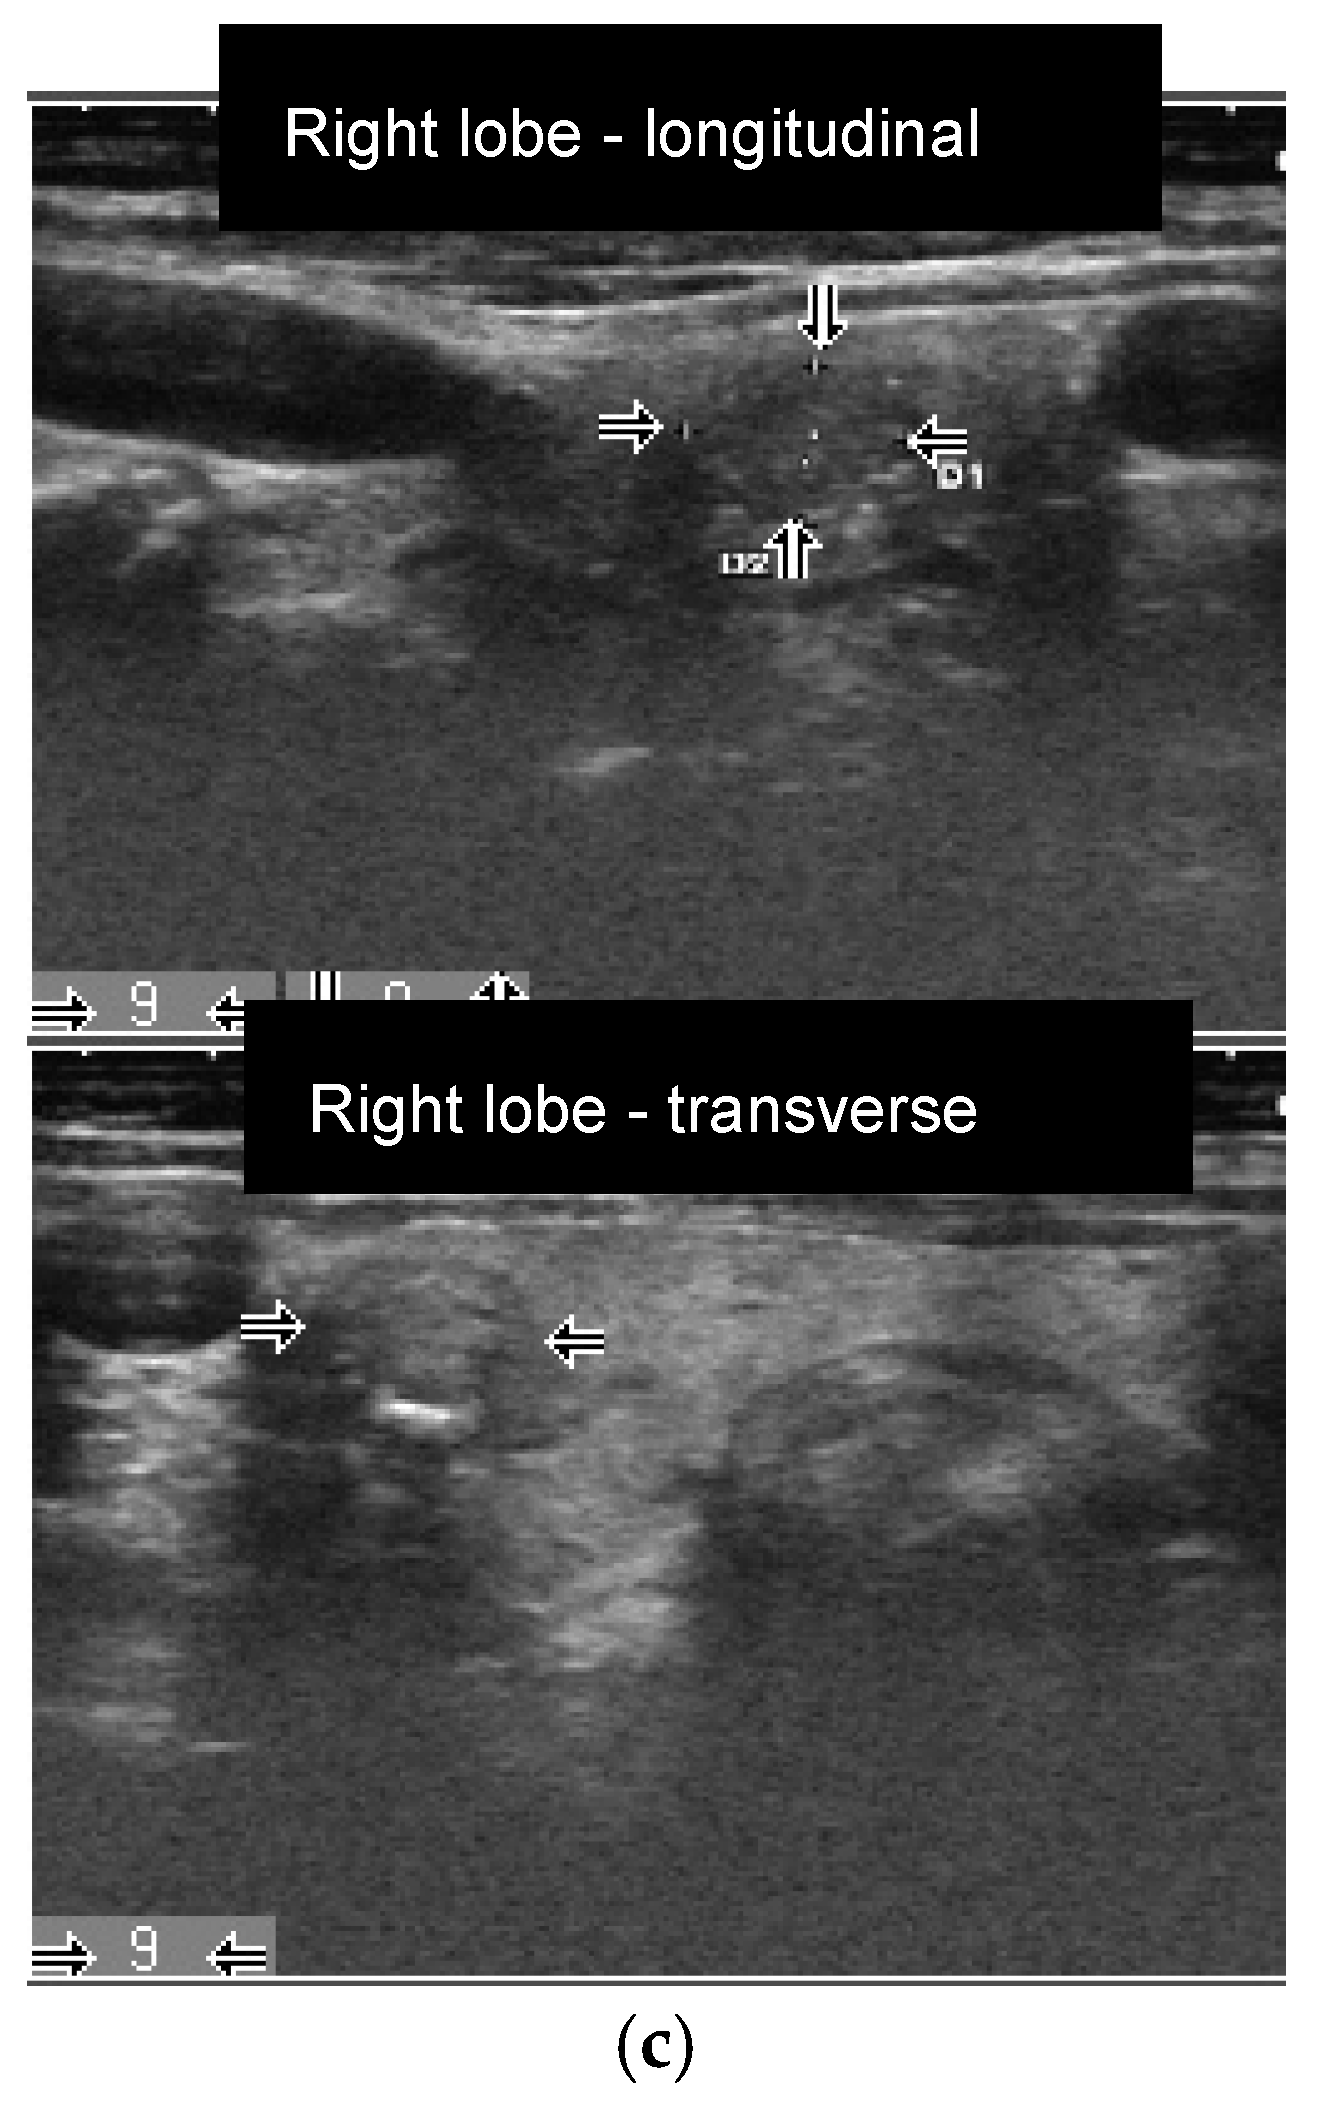

Figure 2.

Female patient (77 years old) with an autonomously functioning thyroid nodule (AFTN) (99mTc-pertechnetate image) in the right lower lobe (longitudinal and transverse images, nodule size: 16 × 17 × 21 mm, volume: 2.9 mL, arrows). (a) Before radioiodine therapy (RIT) (2016, TSH value < 0.1 mU/L, suppression with Levothyroxine) with 498 MBq (510 Gy). TIRADS classification: Kwak-TIRADS 4C (solid composition, microcalcifications, taller-than-wide shape, irregular margins); EU-TIRADS 5 (microcalcifications, taller-than-wide shape, irregular margins); (b) The same patient 7 months (follow-up 1, FU1) after RIT. The thyroid nodule size decreased to 9 × 11 × 11 mm (volume: 0.5 mL, arrows). Scintigraphy with 99mTc-pertechnetate shows a hypofunctioning area in the lower right lobe, which reflects a therapeutic response (TSH value 1.2 mU/L, no thyroid medications). TIRADS classification: Kwak-TIRADS 4C (solid composition, isoechoic/hypoechoic parts, microcalcifications and macrocalcification, taller-than-wide shape); EU-TIRADS 5 (microcalcifications, taller-than-wide shape); (c) The same patient 12 months after RIT (TSH value 1.2 mU/L, no thyroid medications). The thyroid nodule size at FU2 was 9 × 8 × 9 mm (volume: 0.3 mL, −90% reduction, arrows). TIRADS classification: Kwak-TIRADS 4C (solid composition, mildly hypoechoic, microcalcifications and macrocalcification); EU-TIRADS 5 (microcalcifications).